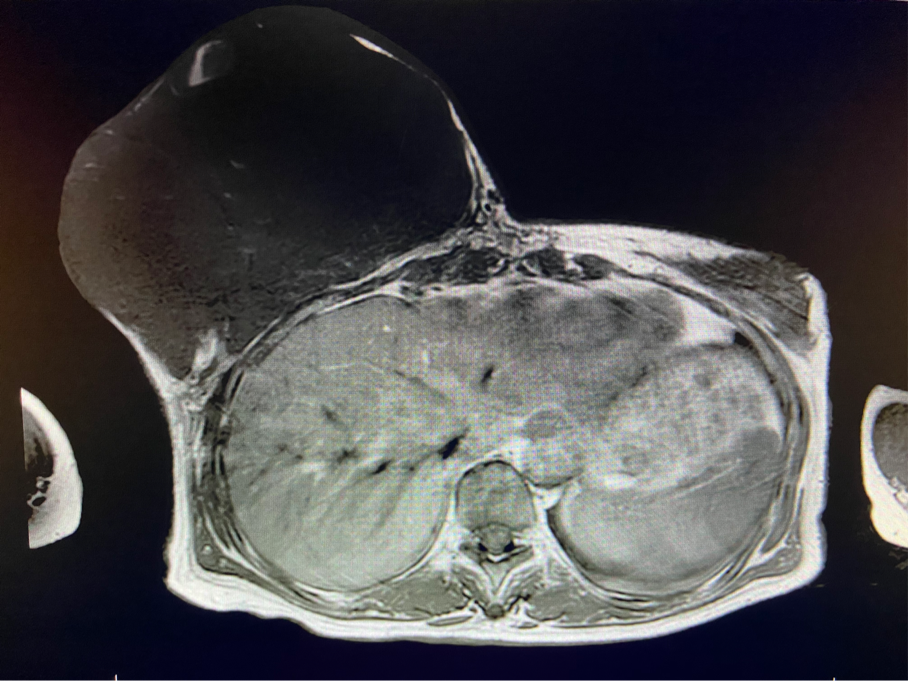

2周前,王女士的右乳外下方皮膚破潰,伴大量滲液,還發(fā)出陣陣惡臭。經(jīng)多方打聽,王女士從外地來到西安國際醫(yī)學(xué)中心醫(yī)院甲乳外科劉曉敏主任處就診。入院后,迅速完善了一系列相關(guān)術(shù)前檢查:王女士的雙乳外形不對稱,右乳約22?20cm,皮膚水腫明顯并可見靜脈曲張。右乳外下象限皮膚可見局部破潰,創(chuàng)面有3處,共約6?4cm大小,創(chuàng)面呈暗紅色,伴有血性滲出及惡臭,局部皮膚溫度升高。右側(cè)腋窩可觸及腫大淋巴結(jié)。

該患者右乳巨大腫物術(shù)前初步考慮乳腺葉狀腫瘤可能,因腫瘤太大,幾乎遍及整個右側(cè)乳房,為保證“無瘤原則”,術(shù)中切除范圍位置未知,極有可能出現(xiàn)皮瓣缺損。于是,經(jīng)過和整形醫(yī)院郭樹忠院長、整形外科王愛武主任的討論,提供了兩種手術(shù)方式,一是創(chuàng)面修復(fù)(植皮或轉(zhuǎn)移皮瓣修復(fù)創(chuàng)面),二是乳房再造,與患者及家屬溝通后,決定先解決腫物,3年病情不再復(fù)發(fā)后,可以再考慮乳房重建。